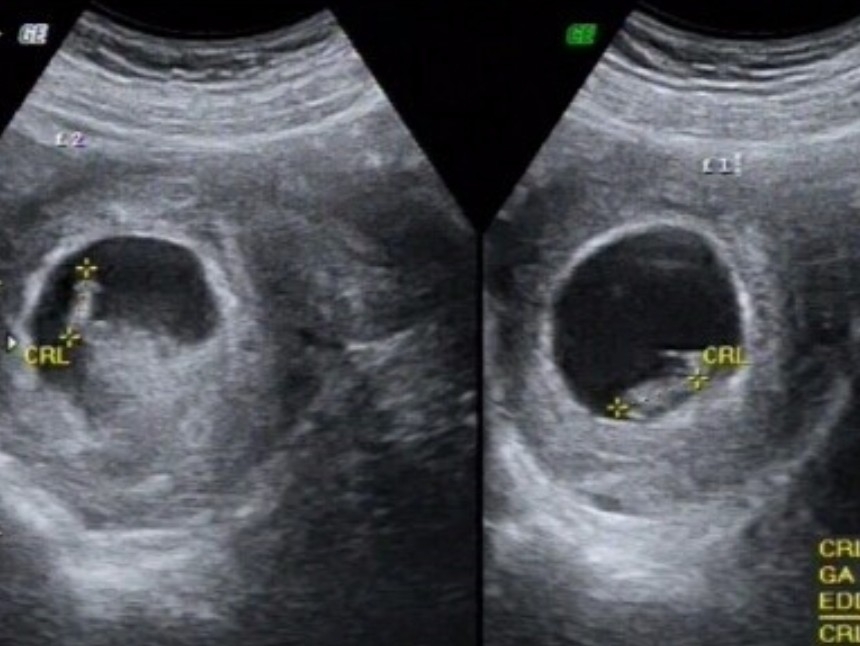

그렇게 티격태격거리며 병원으로 갔고,

여주의 이름이 불릴때까지 그들은

지난번 초음파 검사때 찍어둔 사진만 바라봤다.

초음파를 이리저리 보던 의사는 끝내 말이없었고

어....